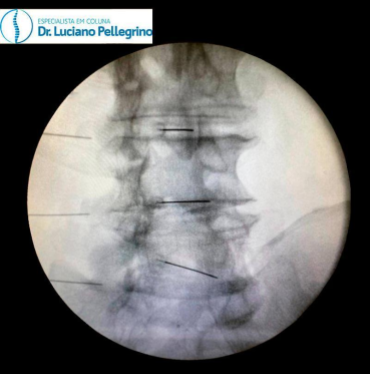

hérnia cirurgia

Endoscopia da coluna para hérnia de disco (visão do RX)

4. INFILTRAÇÃO NA COLUNA

Outra alternativa com uma boa taxa de resposta para tratar os sintomas da hérnia de disco é a infiltração na coluna. Esse procedimento consiste na injeção de medicamentos em pontos específicos da coluna a fim de controlar processos inflamatórios e sintomas dolorosos.

Além de não precisar de cortes e nem de anestesia geral, a infiltração na coluna costuma ser rápida – o procedimento leva em torno de 30 a 60 minutos. Geralmente, o paciente pode receber alta poucas horas depois do procedimento.

Dependendo da reação do organismo e da avaliação do médico especialista em coluna, a infiltração na coluna pode reduzir significativamente os sintomas e eliminar a necessidade de uma cirurgia de maior porte.

É importante frisar que a infiltração na coluna não remove a hérnia de disco. Entretanto, permite uma melhora da dor e processo inflamatório de forma que o organismo “ganhe tempo” para que ocorra uma reabsorção natural da hérnia de disco ao longo do tempo.

Infiltração na coluna para hérnia de disco